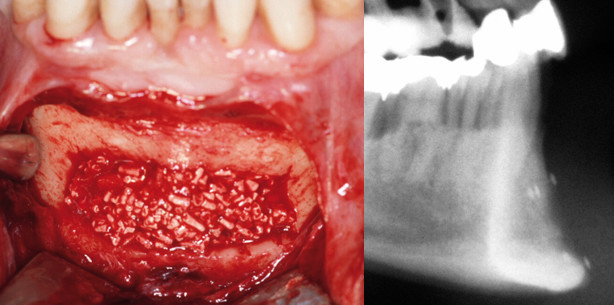

Im Wesentlichen verwenden wir pflanzliche Materialien in unserer Klinik bei Sinusbodenelevationen, aber auch zur Rekonstruktion von Knochenentnahmestellen aus dem Kinnbereich.

Beim konventionellen Verfahren wird die Mischung in den durch die Verschiebung der Kieferhöhlenschleimhaut neu geschaffenen Raum eingebracht. Erst nach einer Einheilzeit von sechs bis neun Monaten ist die neue Knochensubstanz hinreichend für die folgende Implantation belastbar. Bei der Schichttechnik dagegen verwenden wir das Biomaterial als erste Schicht unterhalb der abpräparierten Kieferhöhlenschleimhaut, was vor Resorptionen durch den Pneumatisierungsdruck schützt. Unterhalb des Knochenersatzmaterials wird zerkleinerter autogener Knochen eingefüllt, sodass die Implantate ausschließlich mit Eigenknochen in Kontakt stehen. Das laterale Sinusfenster wird anschließend mit Knochenersatzmaterial und einer nicht resorbierbaren Titanmembran (FRIOS® BoneShield) verschlossen.

Die Schichtstärke ergibt sich aus der Situation. Wenn wir simultan implantieren, versuchen wir die Implantatoberfläche komplett mit Eigenknochen abzudecken. Gehen wir zweiphasig vor, also augmentieren zunächst und implantieren nach einem Vierteljahr, verfolgen wir das gleiche Prinzip: Augmentation kranial mit purem Biomaterial und krestal mit autogenem Knochen: Ziel ist, eine Gesamthöhe von mindestens 8 mm zu erzielen, was eine gute Implantatstabilisierung erlaubt. Das osteokonduktive Material hat also eine Platzhalterfunktion.